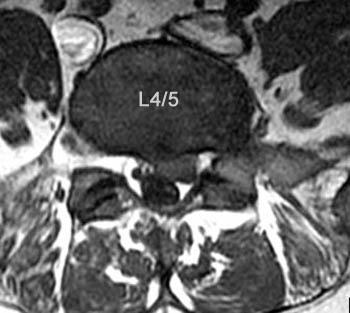

1. A 79-year old man falls sustaining a hyperextension injury to his neck. A lateral radiograph, CT scan and MRI are seen in Figures A through C. On motor examination, he has 3/5 strength in his deltoids, elbow and wrist flexors and extensors. He has 4/5 strength in his hip flexors, knee flexors, extensors, ankle dorsiflexors and plantarflexors. Sensation is preserved in both his upper and lower extremities as well as his sacral segments. Injury to which of the following tracts contributes greatest to his motor function deficits?

DISCUSSION: The clinical scenario describes a patient with central cord syndrome, resulting in an injury to his lateral corticospinal tract. Figures A through C show a spondylytic spine with central narrowing and CSF effacement that is worse at the C4-5 level. The lateral corticospinal tract is the main descending motor tract (Illustration A). Its anatomic position places the upper extermity motor tracts at greater risk than the lower extremity tracts. As such, injury to the lateral corticospinal tract is characterized by upper greater than lower extremity involvement and motor deficits being more pronounced than sensory deficits.